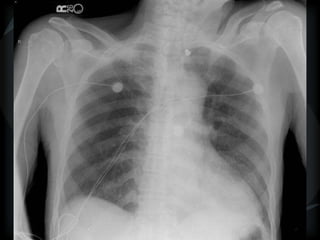

PHTN – PA 39mm

39.2mm

PHTN and septal thickening

? PVOD